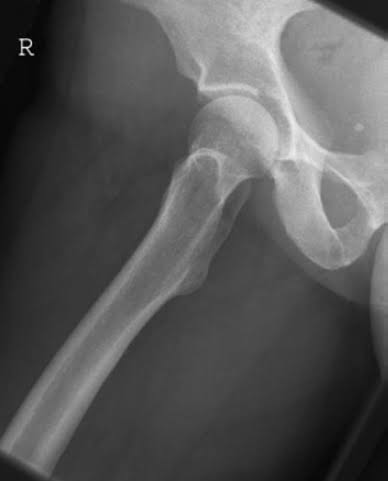

Pelvis Posterior Oblique

(Lauenstein's projection)

Patient की टांगों को extend करके patient को x-ray table पर supine सुलाते है। patient का msp x-ray table के long axis से coincide होने चाहिए। patient को affected side की ओर 45° डिग्री rotate करते है। साथ ही hip को 45° degree abduct और 45° डिग्री flex करते है। तथा non-opaque pads के द्वारा इस position को support दिया जाता हैं । जांघ के lateral aspect को table top के cantact में लाने के लिए knee को flex करते है। इससे knee भी lateral position में आ जाता हैं। examine के दौरान दूसरे limb को उठाकर limb के पीछे रखते हैं support रखने के लिए।

इसमे एक 24×30cm की cassette का use किया जाता हैं। तथा bucky tray में longitudinally तथा सम्भवतः obliquely रखते है। cassette के centre को groin के femoral pulse के level पर रखते है तथा femur का upper third part शामिल होना चाहिए। कैसेट का upper border anterior superior iliac spine के level पर होना चाहिए।

X-ray beam के centre को affected side के groin के femoral pulse पर तथा cassette के लम्बवत देते है।primary beam को examination के दौरान area पर collimated जरूर करना चाहिए।